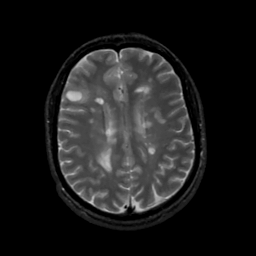

MR Study #8, March 31, 1991 -- Slice #33

[Home][Help][Clinical][Tour 1][Tour 2] Slice 33